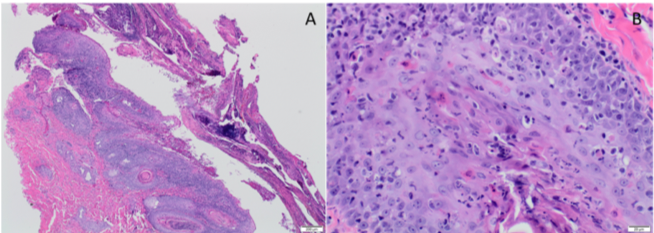

| Figure A and B Histopathology |

The microscopic lesions were consistent with Erythema Multiforme (EM) with likely secondary pyoderma. All the biopsies submitted had similar lesions on microscopic examination from multiple locations. The epidermis was hyperplastic with multifocal erosion and ulceration with marked crusting and cell debris. (Figure A) Both the epidermal and follicular epithelium had multifocal apoptosis of keratinocytes at multiple levels of epidermal layers along with lymphocytic infiltration in the epidermis. There were areas of interface dermatitis with predominantly lymphocytic infiltration. (Figure B)